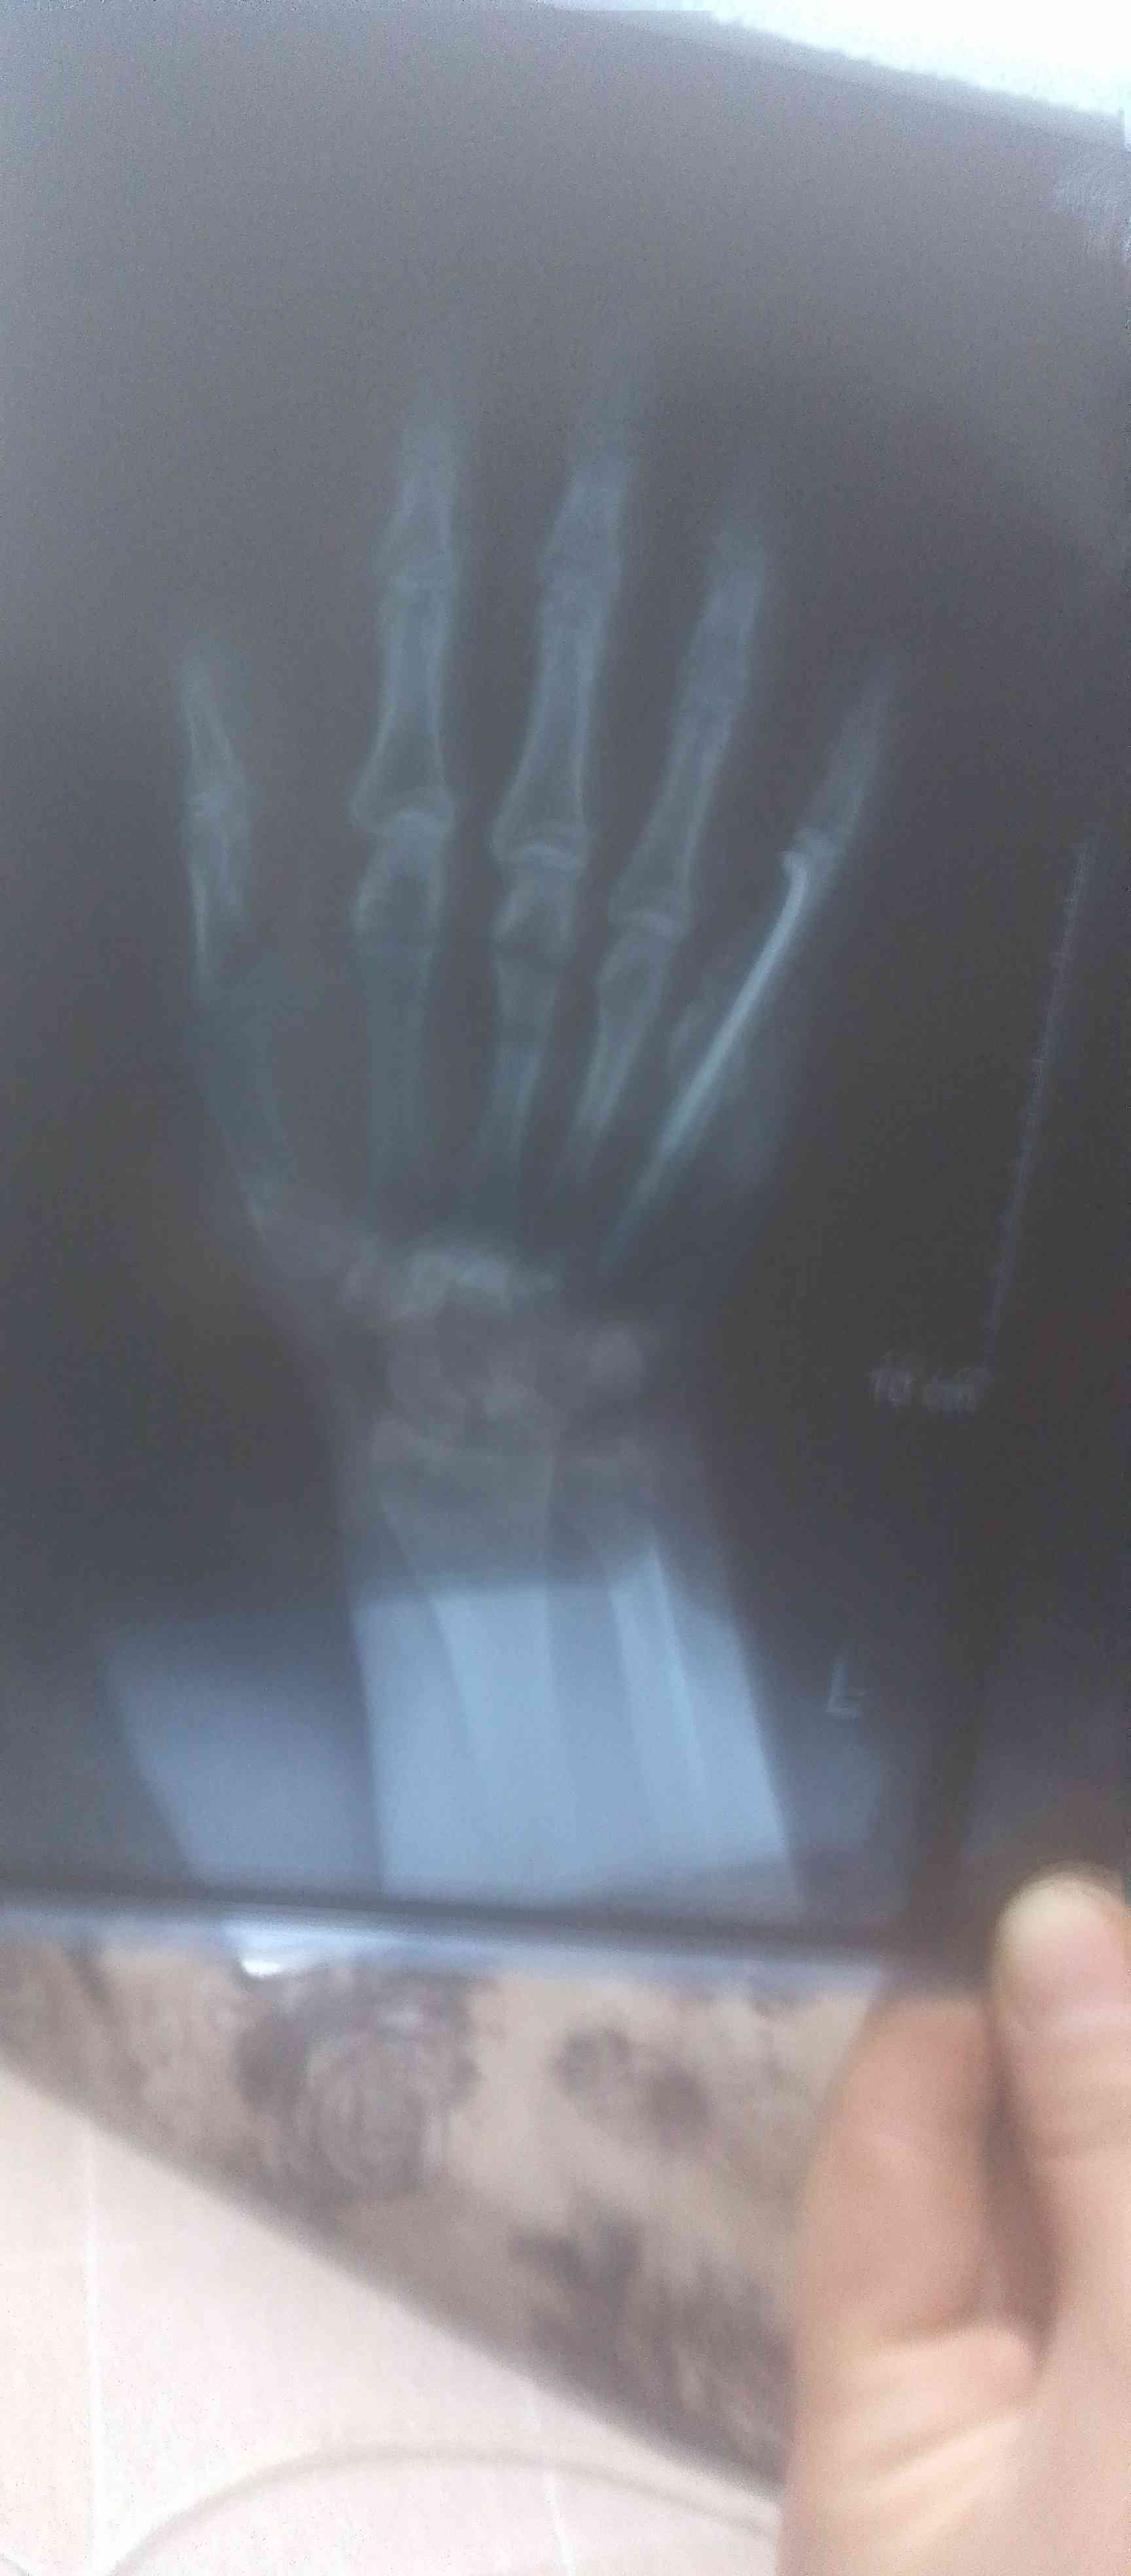

كان لدي كسر فى مشط اليد في عظمة الخنصر وبعد إلتئام العظم وبعد نزع الجبيرة لاحضت وجود انتفاخ مكان الكسر...